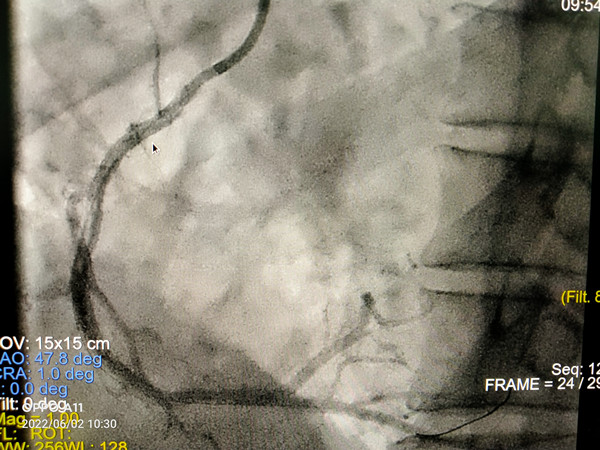

在我院心外科裴斐主任医师,麻醉科刘鹏斌主任医师、罗斌主治医师,超声科韩东刚副主任医师、金鑫主治医师,曹春晖护士长领导的护理团队等多学科协助下,韩振华主任、王新宏副主任医师、刘小军主治医师等先为患者行冠脉造影提示右冠近段95%狭窄(图1),先行PCI干预,右冠植入3.0x22mm支架1枚(图2)。后成功为患者植入TAV24mm VitaFlow瓣膜系统,DSA造影显示主动脉瓣位置良好,未见明显瓣周漏(图3),左右冠脉造影正常,术后即刻心脏超声示最大跨瓣流速129cm/s,最大跨瓣压差7mmHg(图4),顺利结束手术。